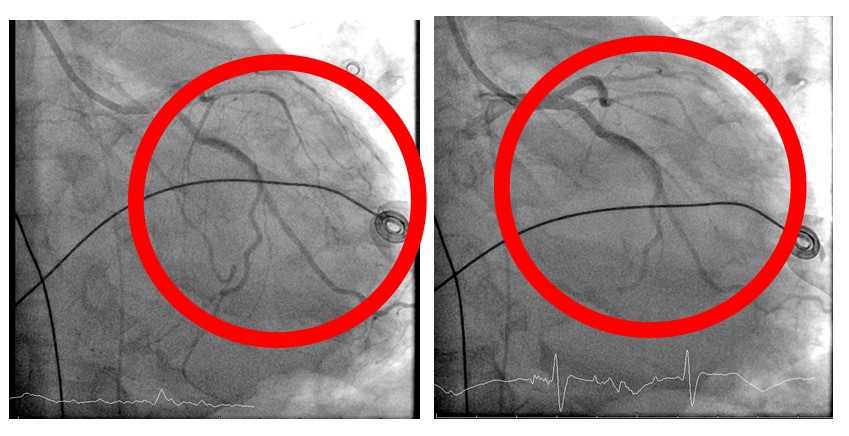

在葉克膜支持下,心臟內科張偉俊醫師立即安排緊急心導管檢查,歷時7小時完成高難度冠狀動脈鈣化旋磨與震波氣球治療(Rota-Shock策略),成功打通三條嚴重阻塞之冠狀動脈並完成支架置放,同步放置主動脈內氣球幫浦(IABP),以提升心臟輸出量、減輕心臟負荷並穩定血流動力。

在跨科團隊密切合作與整合性重症照護下,患者病況逐步穩定,心肺功能明顯改善,後續順利移除葉克膜及主動脈內氣球幫浦等維生設備,成功脫離加護病房,目前已轉入普通病房持續治療。